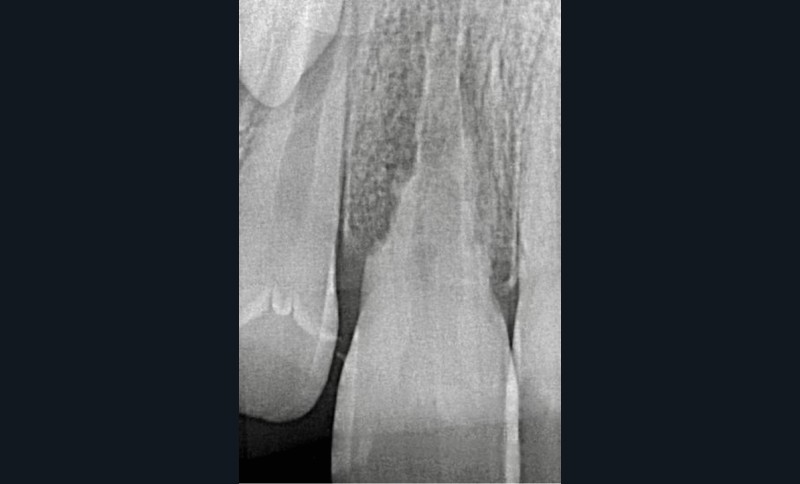

Les RREI se manifestent par des signes de parodontite apicale : douleur, gonflement, sensibilité à la percussion ou à la palpation, fistule ou dyschromie de la couronne. En général, la dent affectée présente une réponse négative aux tests de sensibilité pulpaire [5]. L’examen radiographique montre des zones radioclaires irrégulières (aspect déchiqueté) autour de la racine lorsque la résorption est active. Le canal radiculaire reste visible et bien identifiable. Dans les cas avancés de résorption, la racine peut être complètement résorbée. Un examen 3D (CBCT : Cone Beam Computed Tomography) est recommandé pour aider au diagnostic et à la prise en charge de la RREI qui, cliniquement, semble traitable [6].

Après un traumatisme dentaire, un suivi clinique et radiographique régulier est essentiel pour détecter les premiers signes de RREI. La pulpe des dents permanentes immatures peut survivre ou se revasculariser spontanément après une luxation, ce qui justifie d’éviter un traitement…